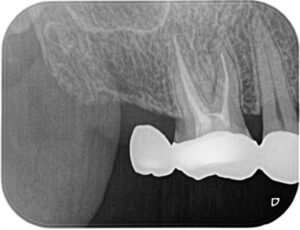

術前:一見根管治療は十分にされているように思えますが、近心根に破折器具および小さな根尖病変を認めます。